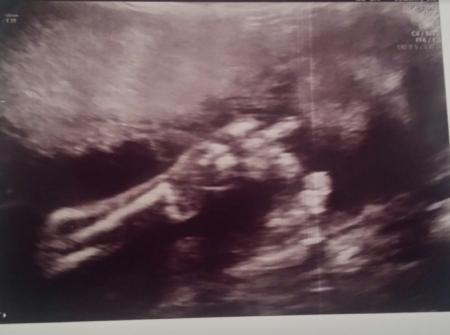

Hier etwas lustig...bin in der 25. Ssw und hatte vor kurzem die feindiagnostik..mein kleiner hat sich total versteckt und wollte sich nicht zeigen...die ärztin meinte sie würde gerne mal was ausprobieren..ich sollte aufstehen kleine Übungen machen (beugen, in die hocke etc) dann würde er sich drehen und zeigen.....und was kommt da

streckt er uns tatsächlich den Mittelfinger raus...die ärztin war total überrascht und hat mir das bild ausgedruckt...die berliner Mentalität hat er schon mal ![]()